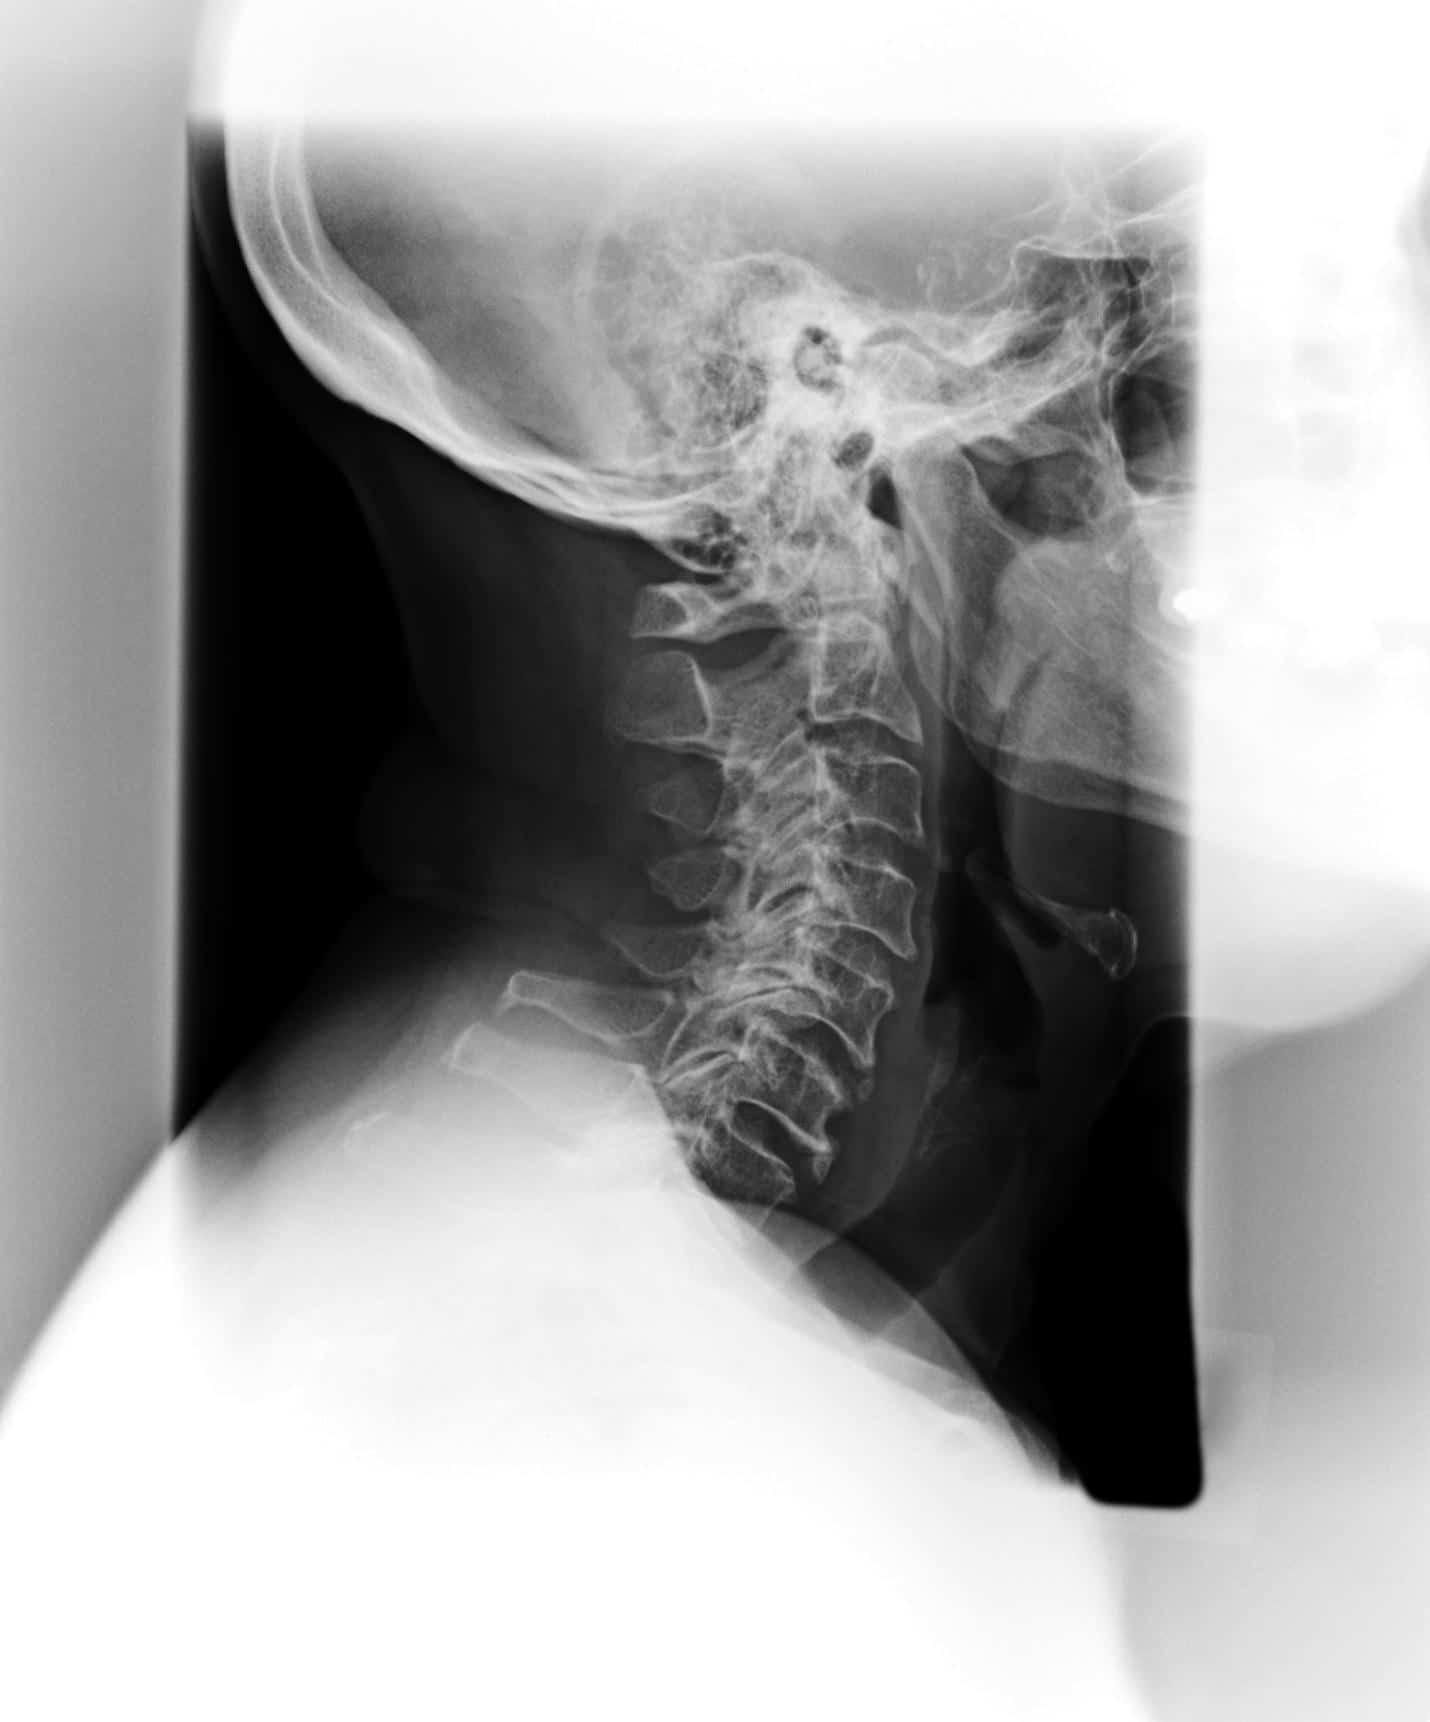

PHASE I Degeneration

The first phase of subluxation degeneration sees the basic and normal curve of the spine alter. This doesn’t necessarily represent damage, but it is a symptom of changing space between the discs. Generally, this phase goes unnoticed because it carries no pain. However, proper chiropractic care can diagnose this issue an stop further misalignment and degeneration.